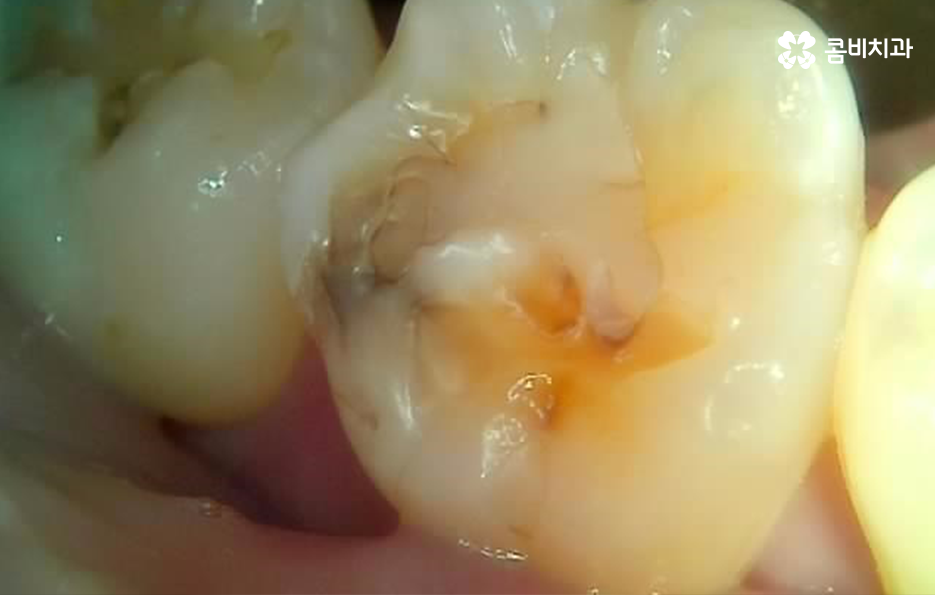

어금니 레진으로 치료 했던 부위의 주변에 검게 변색되었어요. 그리고 주변이 깨졌어요

어금니 레진 치료 후에 레진 자체가 깨지거나 주변 치아가 깨진 경우에는 당장 안아파도 치과에서 재치료를 받는 것이 추가적인 파절을 예방하고 치아 내부로 충치가 발생되는 것을 예방할 수 있으며 특히 주변이 검게 변색되는 경우에는 착색인 경우도 있지만, 2차 충치가 이미 진행된 경우가 많기 때문에 통증과는 무관하게 치과 방문을 권하고 있어요